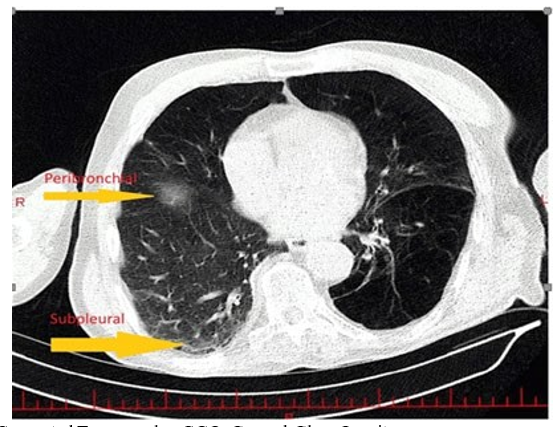

In the laboratory evaluation, tests were conducted including Complete Blood Count (CBC), Blood Urea Nitrogen (BUN), creatinine, sodium, potassium, Prothrombin Time (PT), Partial Thromboplastin Time (PTT), International Normalized Ratio (INR), C-Reactive Protein (CRP), Erythrocyte Sedimentation Rate (ESR), troponin, White Blood Cell Differential (WBC diff), platelet count, urinalysis, and urine culture. The INR was 1.4. In the imaging evaluation, a High-Resolution Computed Tomography (HRCT) scan of the lungs was performed, revealing centrilobular emphysema in both lungs, consolidation at the base of the right lung, and ground-glass opacity at the base of the left lung (Figures 1 and 2).

HRCT: High-Resolution Computed Tomography, GGO: Ground-Glass OpacityFigure 2: The HRCT Scan Shows Areas of GGO Located in the Subpleural and Peribronchial Regions. These GGOs indicate hazy areas of increased lung attenuation that may suggest inflammation, infection, or early fibrosis in these specific Lung Zones